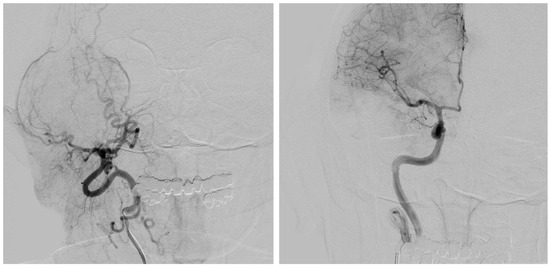

- Vascularization: Being a particularly delicate area considering the vascular and other structures present in the area, these must be identified. Medially to the glenoid fossa, besides the internal maxillary artery, there are the foramen ovalis, through which there is the mandibular nerve V3 (third division of the trigeminal nerve CN V), and the the foramen spinosum, which gives passage to the middle meningeal artery. Posteromedially instead, there are the foramen lacerum; the carotid canal, which contains the internal carotid artery; the jugular hole, which gives passage to the glossopharyngeal nerve (CN IX), vagus nerve (CN X), and accessory nerve (CN XI), and in its posterolateral originating from the sigmoid sinus, gives rise through the hole to the internal jugular vein; the stylomastoid hole, which contains the stylomastoid artery and the facial nerve (CN VII). So, to segment and reconstruct arterial vasculature, a 3D time-of-flight (TOF) MRI with the following parameters was acquired: TR = 25.0 ms; TE = 7.15 ms; slice thickness = 0.5 mm; in-plane resolution: 0.4 × 0.4 mm; slice GAP = −25%; matrix 256 × 256 px. To highlight venous structures, a phase-contrast MR venography sequence was performed.

- Computed Tomography Angiography (CTA): When a free bone flap was planned (e.g., free fibula flap, free iliac crest flap, etc.) in order to perform a mixed autologous/alloplastic eTMJR, the patient underwent a CTA, given the need to know the anatomy of the vascular pedicle.